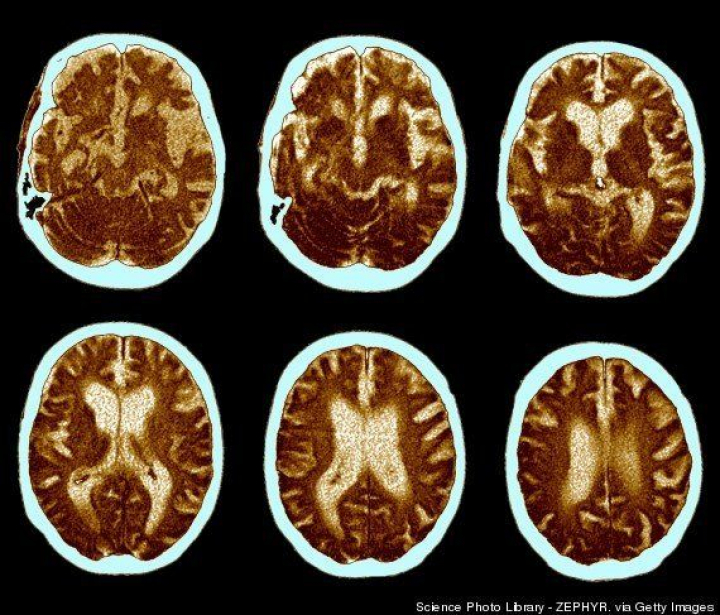

4. No hay inmunidad al Alzheimer, pero sí se desarrolla de forma más tardía

Cualquiera puede padecer Alzheimer, pero las personas bilingües desarrollan esta enfermedad cuatro o cinco años más tarde que las monolingües, de acuerdo con los descubrimientos presentados en el encuentro de 2011 de la American Association for the Advancement of Science. En el estudio participaron 450 pacientes con Alzheimer, la mitad de los cuales habían hablado dos lenguas la mayor parte de sus vidas.